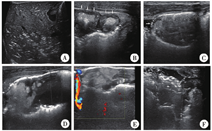

对差异有统计学意义的超声征象如肠壁变薄、肠壁分层消失、肠壁血流信号消失、病变肠管蠕动消失、肠管扩张、透声差的积液,进行两两组合分析,发现肠管蠕动消失与肠壁分层消失组合对NEC危重症患儿的识别可获得较高的敏感度(93.3%)和特异度(93.3%)。典型病例超声图像见图2。

A:门脉积气;B:肠壁增厚,分层不清(箭头); C:局部肠壁变薄伴点状肠壁积气(箭头); D:局部肠管扩张(测量键); E:肠壁血流信号消失;F:透声差的积液(测量键)